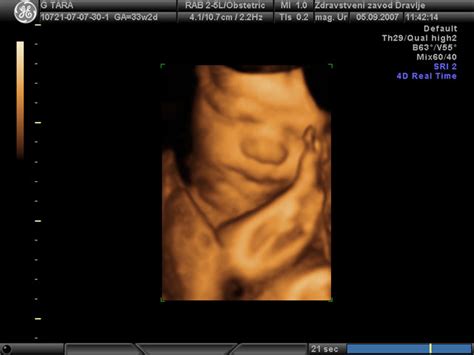

V 15. tednu nosečnosti je vaš otrok velik približno kot jabolko, meri okoli 12,7 cm in tehta približno 57 gramov. Njegovo telo se še vedno hitro razvija. Koža je še vedno precej prosojna, zato so vidne tudi žile. Celotno telo je prekrito z nežnimi, tankimi dlačicami, imenovanimi lanugo. Vsaka od teh drobnih dlačic ima žlezo lojnico, ki proizvaja sirasto maz (vernix caseosa), snov, ki ščiti otrokovo občutljivo kožo pred amnijsko tekočino in mu pomaga pri porodu. Že v tem tednu lahko na ultrazvočnem pregledu opazite, kako vaš otrok sesa palec, stiska pest ali se refleksno smeji. Čeprav je še prezgodaj, da bi začutili prve gibe, se otrok že aktivno premika v maternici. Kosti vašega otroka postajajo trdnejše, in če bi zdaj opravili rentgensko slikanje, bi bile vidne.